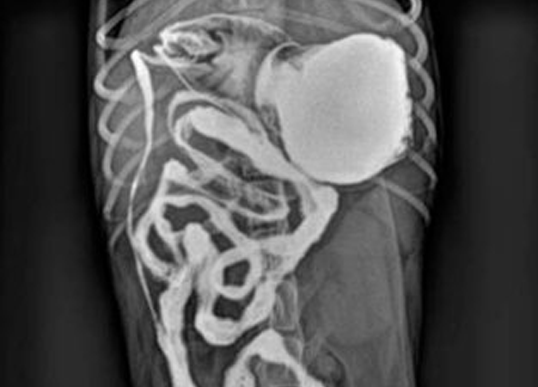

조영촬영 검사(Contrast study) - 위장관 & 비뇨기 조영

식도, 위장관, 비뇨기계, 외이도에 조영제를 투여하여 검사하는 방법입니다. 일반 X-ray 촬영과 더불어 보다 정확한 진단을 위해 식도, 위장관, 비뇨기계, 외이도에 조영제를 투여하여 개통성과 이물의 여부를 확인하고 있습니다. 조영 검사를 통해 위장관 이물, 폐색, 중첩, 방광파열, 결석에 의한 폐색, 외이염, 고막파열 등을 진단할 수 있습니다.